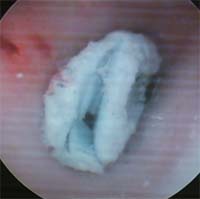

9歳小学3年生 右耳に紙を入れた 母がピンセットで取ろうとするも 取れず。右上にひっかき傷 前週は左耳に紙を入れ受診 2021年2月5日  |